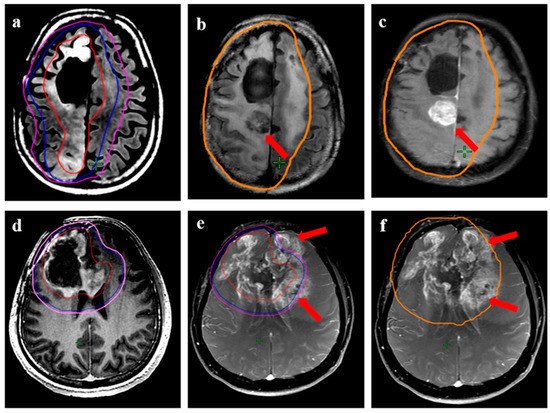

Figure 7.

Distant relapse following re-irradiation in a 38-year male with IDH-mutant astrocytoma with transformation (radiological) to grade 4 during reirradiation. (a,b) show the target volumes (GTV: red, CTV: blue; PTV: magenta) on T1w contrast and T2w images. The GTV encompassed all the T2w altered signals, including the enhancing disease, while CTV was 10–15 mm expansion along the brain parenchyma. (c) represents the response in the primary re-irradiated region 6 months following ReRT, while the lower panel shows axial (d), coronal (e), and sagittal (f) T1w contrast MRI from the same time-point demonstrating distant areas of recurrent disease (arrow) beyond the 95% isodose line (orange).